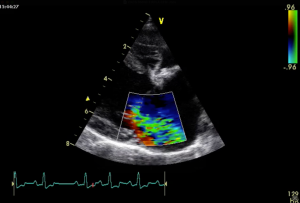

• Pathophysiology of PE

• Causes and prognosis of different types of PE

• Diagnosis

• Management, including draining and surgical options